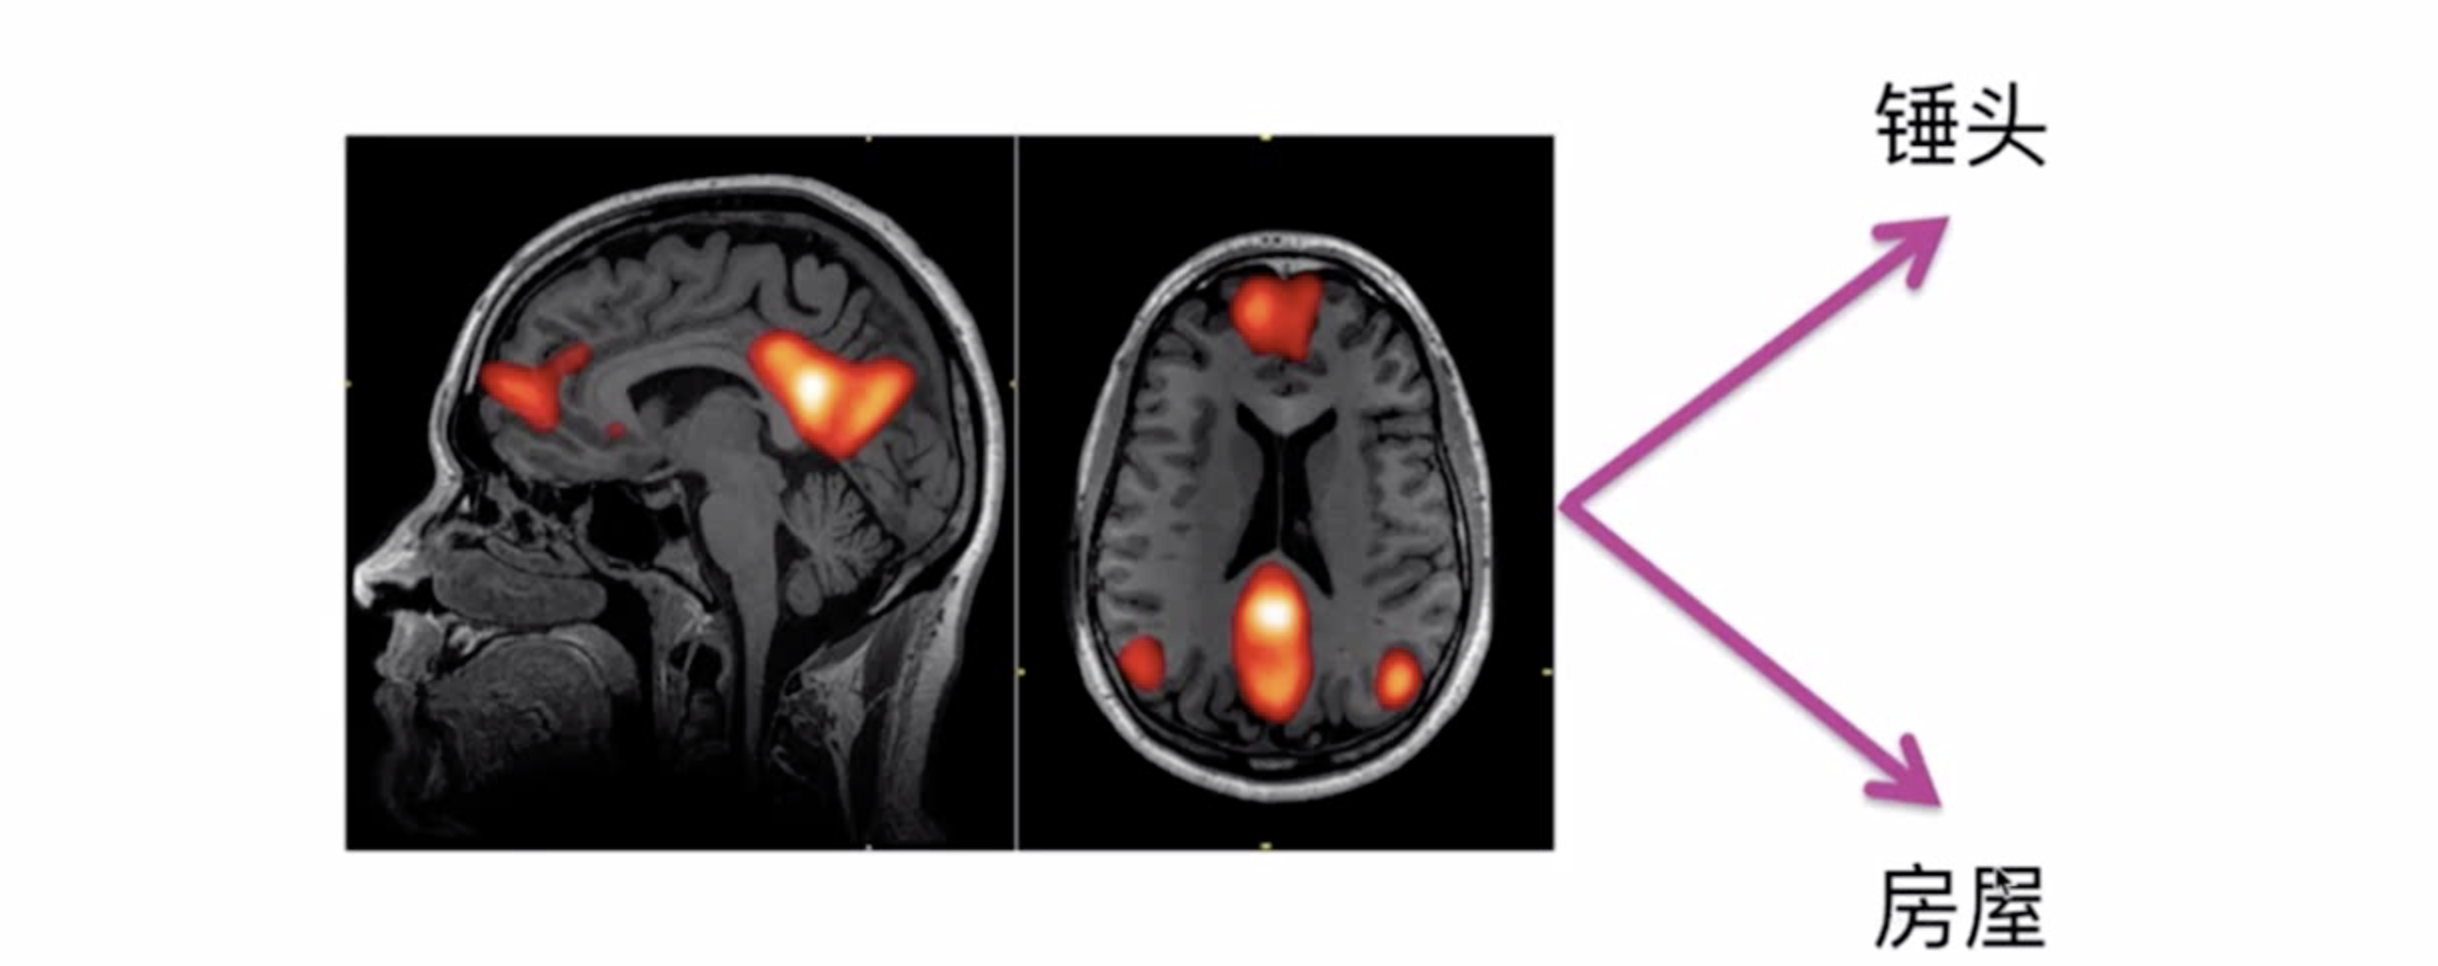

读懂你的心